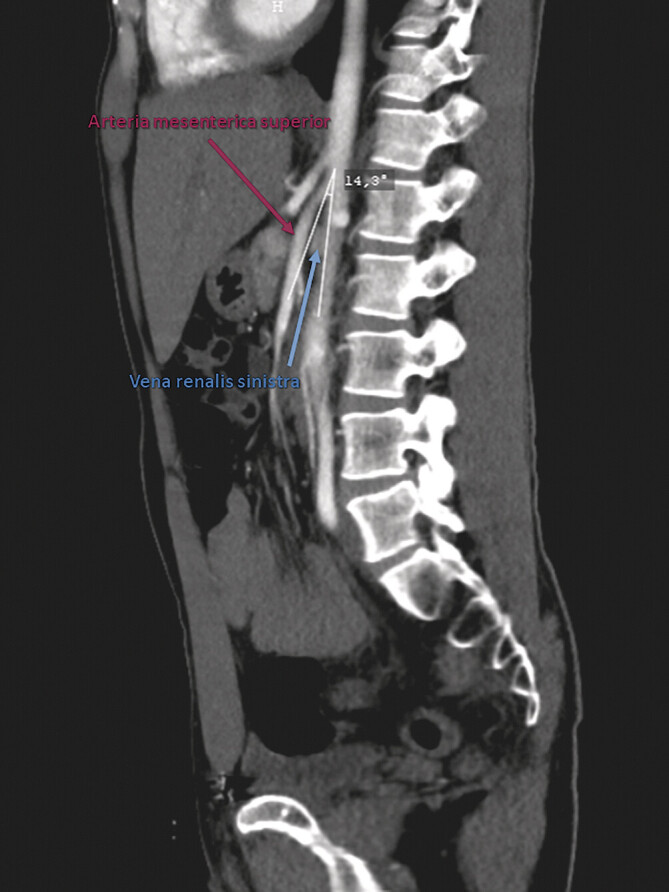

The nut cracker syndrome (NCS) can be considered as an under-diagnosed disease, which the patients have usually suffered from for a prolonged time prior to correct diagnosis and subsequent initiation of adequate therapy. There are several possible therapies, the most promising - transposition of the superior mesenteric artery (SMA) - from the perspective of its aetiopathogenesis - has rarely been used.Based on selective references from the scientific medical literature and our own clinical experiences in vascular medicine, the important characteristics of the "nut cracker" phenomenon and syndrome are described.A topic-related narrative review has been based on a literature search in PubMed using the key words "Nut cracker syndrome", "May-Turner syndrome", "Wilkie syndrome", "aorto-mesenteric angle", "pelvic congestion syndrome".There are diverse symptoms in NCS, which is unspecific; however, in particular, the combination of signs and symptoms associated with a suspicious pathological urine finding may indicate NCS. Duplex ultrasonography and CT-scan are very accurate diagnostic procedures and include an adequate search for simultaneously occurring vascular anomalies. Taken together, clinical findings and laboratory parameters may lead to a patient-specific and graduated therapeutic plan, in which transposition of SMA is a causal, effective and safe procedure, particularly when there are combined vascular anomalies, e.g., the combination of NCS with May-Turner syndrome in young patients.The nutcracker syndrome as venous congestion of the kidney may be a "hard nut". Modern medicine aims at achieving evidence for the best approach by case reports and retrospective cohort studies and can - in the meanwhile - provide a verified diagnostic work-up. In addition, is a therapeutic algorithm comprising a spectrum of highly effective measures, particularly for young patients, who frequently exhibit additional vascular anomalies.